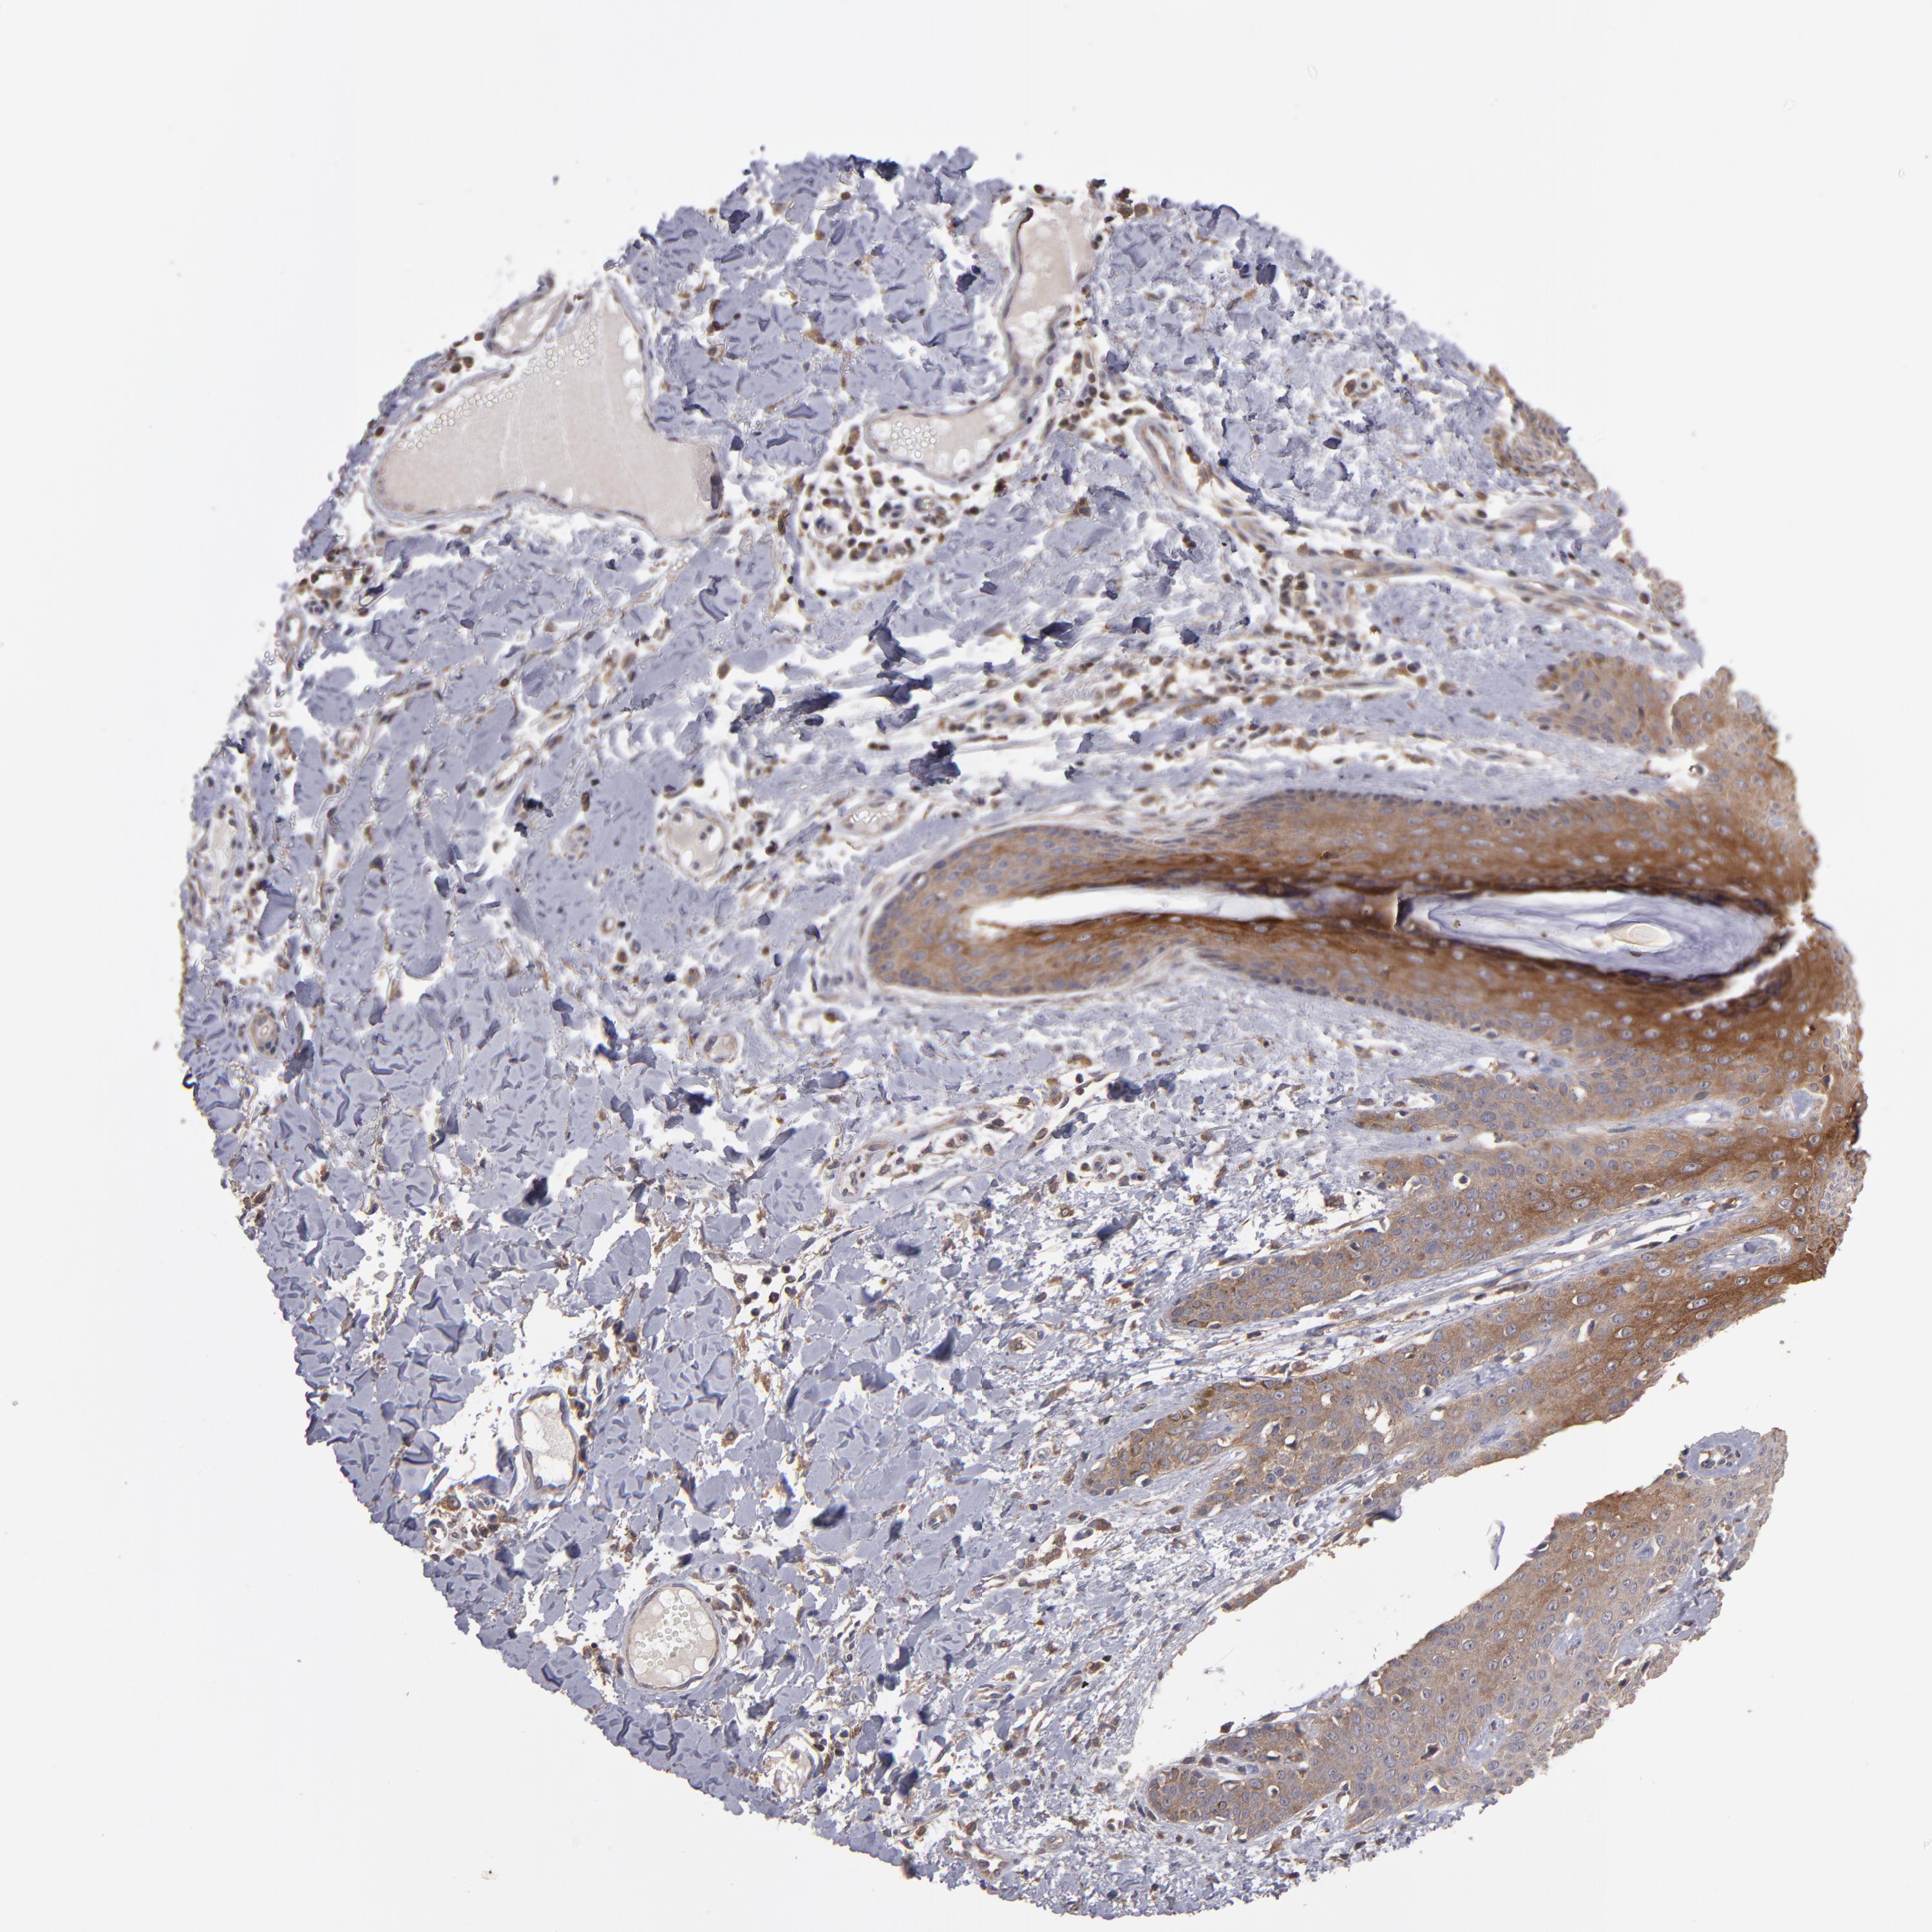

SKIN CANCER - Protein expressioni

A mouse-over function shows sample information and annotation data. Click on an image to view it in a full screen mode. Samples can be filtered based on level of antibody staining by selecting one or several of the following categories: high, medium, low and not detected. The assay and annotation is described here.

Antibody stainingi

Antibody staining in the annotated cell types in the current human tissue is reported as not detected, low, medium, or high, based on conventional immunohistochemistry profiling in selected tissues. This score is based on the combination of the staining intensity and fraction of stained cells.

Each image is clickable and will lead to virtual microscopy that enables deeper exploration of all samples and also displays staining intensity scores, fraction scores and subcellular localization as well as patient and tissue information for each sample.

Antibody HPA003097

Antibody CAB005385

Squamous cell carcinoma, NOS

Basal cell carcinoma

Squamous cell carcinoma, metastatic, NOS

Papilloma, NOS